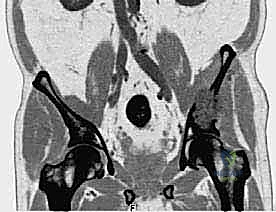

- التصوير المقطعي المحوسب (CT Scan): يقدم صوراً ثلاثية الأبعاد تُظهر بدقة متناهية مدى تدمير القشرة العظمية، وهو الفحص الأهم للتخطيط الجراحي وتحديد خطر حدوث الكسور المرضية.

- التصوير بالرنين المغناطيسي (MRI): الفحص الأفضل لتقييم امتداد الورم خارج العظم إلى الأنسجة الرخوة (العضلات، الأوعية الدموية، الأعصاب) وتقييم مدى إصابة نخاع العظم.